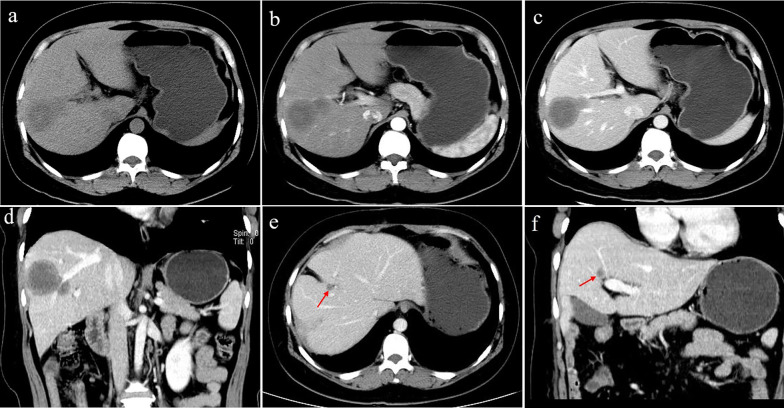

The multifocal nodular type was detected in 9 patients (9/20, 45%). The lesions were located in the right lobe of the liver in only one patient; the whole liver was involved in all of the remaining 8 patients. Coalescent lesions were detected in 6 patients (6/9, 66.7%). One patient showed multiple nodules with calcifications; the other 8 patients showed hypoattenuation compared with the normal liver parenchyma on non-contrast CT imaging. More than 80% of the lesions were peripheral and extended to the liver margin. Retraction of the liver capsule overlying the tumour nodules was detected in 10 lesions of 6 patients. Six patients showed minimal and slight enhancement in the arterial phase; 5 patients showed thin ring-like enhancement. Four patients exhibited slight to moderate progressive centripetal enhancement in the portal phase. In 5 patients, “target” sign enhancement in the portal phase was detected. The “lollipop” sign was observed in 8 lesions of 4 patients (Fig. 3).

Fig. 3.

A 48-year-old female with multifocal nodular type HEH. An axial unenhanced CT image (a) shows multiple round-like low-density lesions in the right lobe of the liver. The lesions show slight enhancement in the arterial phase (b). Axial and coronal reconstruction of portal phase CT images (c, d) show a larger nodule in the right lobe with portal veins entering and terminating in the periphery of the lesion (red arrow). This configuration resembles a typical “lollipop” sign